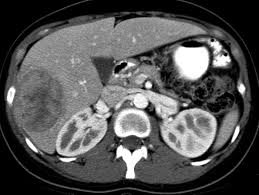

There are two main categories of sarcoma cancer: soft tissue sarcomas and bone sarcomas. Soft tissue sarcomas can include liposarcoma (cancer of fat tissue), leiomyosarcoma (cancer of smooth muscle), and synovial sarcoma, among others. Bone sarcomas primarily refer to osteosarcoma, which typically occurs in the long bones.

Soft Tissue Sarcomas

Soft tissue sarcomas are generally more prevalent and can occur in the arms, legs, abdomen, or chest. Some notable types include:

- Liposarcoma: Originating in fat cells, it can be aggressive and often requires extensive treatment.

- Leimyosarcoma: This sarcoma arises from smooth muscle tissues and is often found in large blood vessels and the gastrointestinal tract.